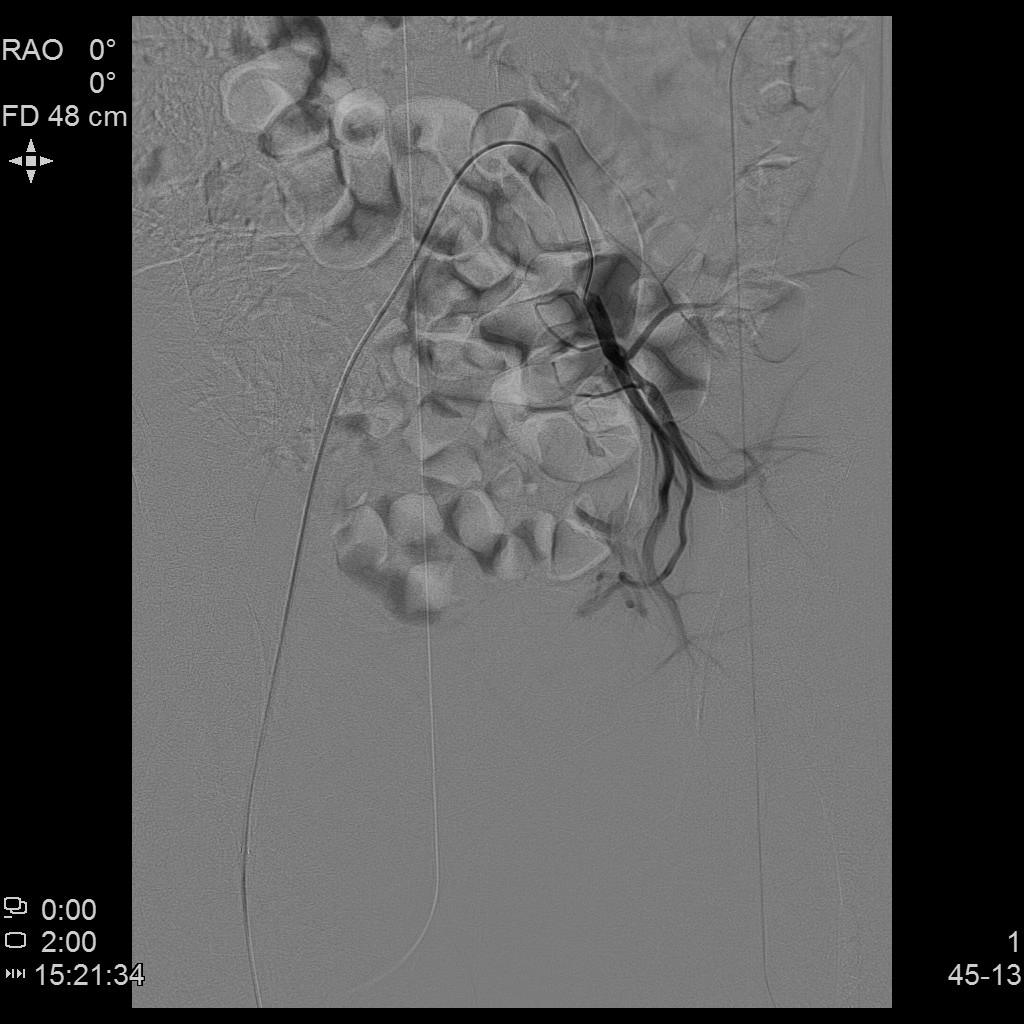

例3

中年患者,发现“子宫腺肌症”10年余,近5年痛经、月经量增多等症状明显加重,导致贫血,严重影响生活质量。

- 术前彩超、磁共振检查显示子宫明显增大,子宫前壁可见弥漫型子宫腺肌症病灶,合并粘膜下、肌壁间子宫肌瘤。

腹主动脉造影

左侧子宫造影

右侧子宫动脉造影

- 术后患者痛经、月经量过多症状迅速缓解,生活质量明显改善。